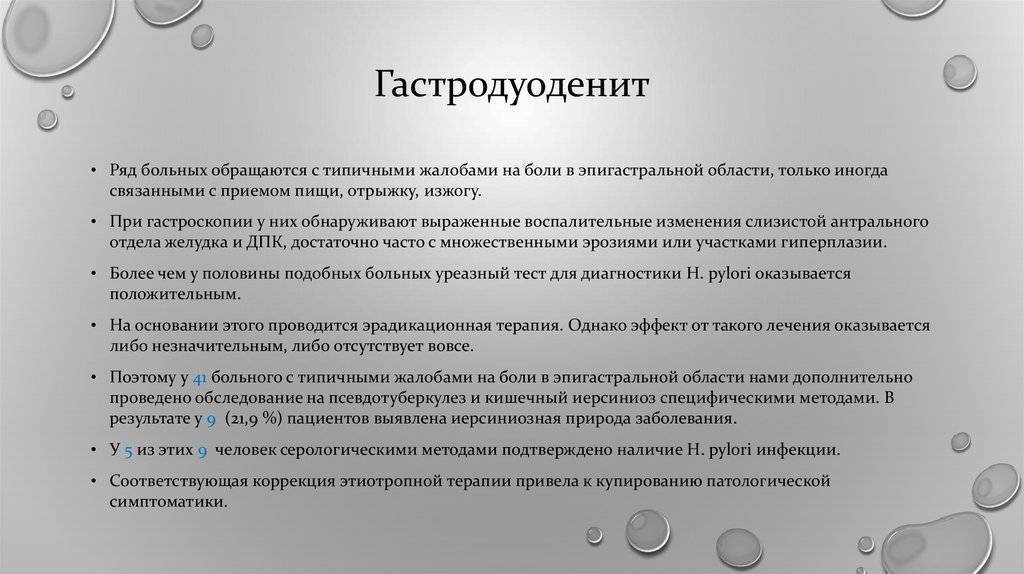

Информация и фотографии о хроническом гастрите и дуодените

Раздел: Фотодневник открытий